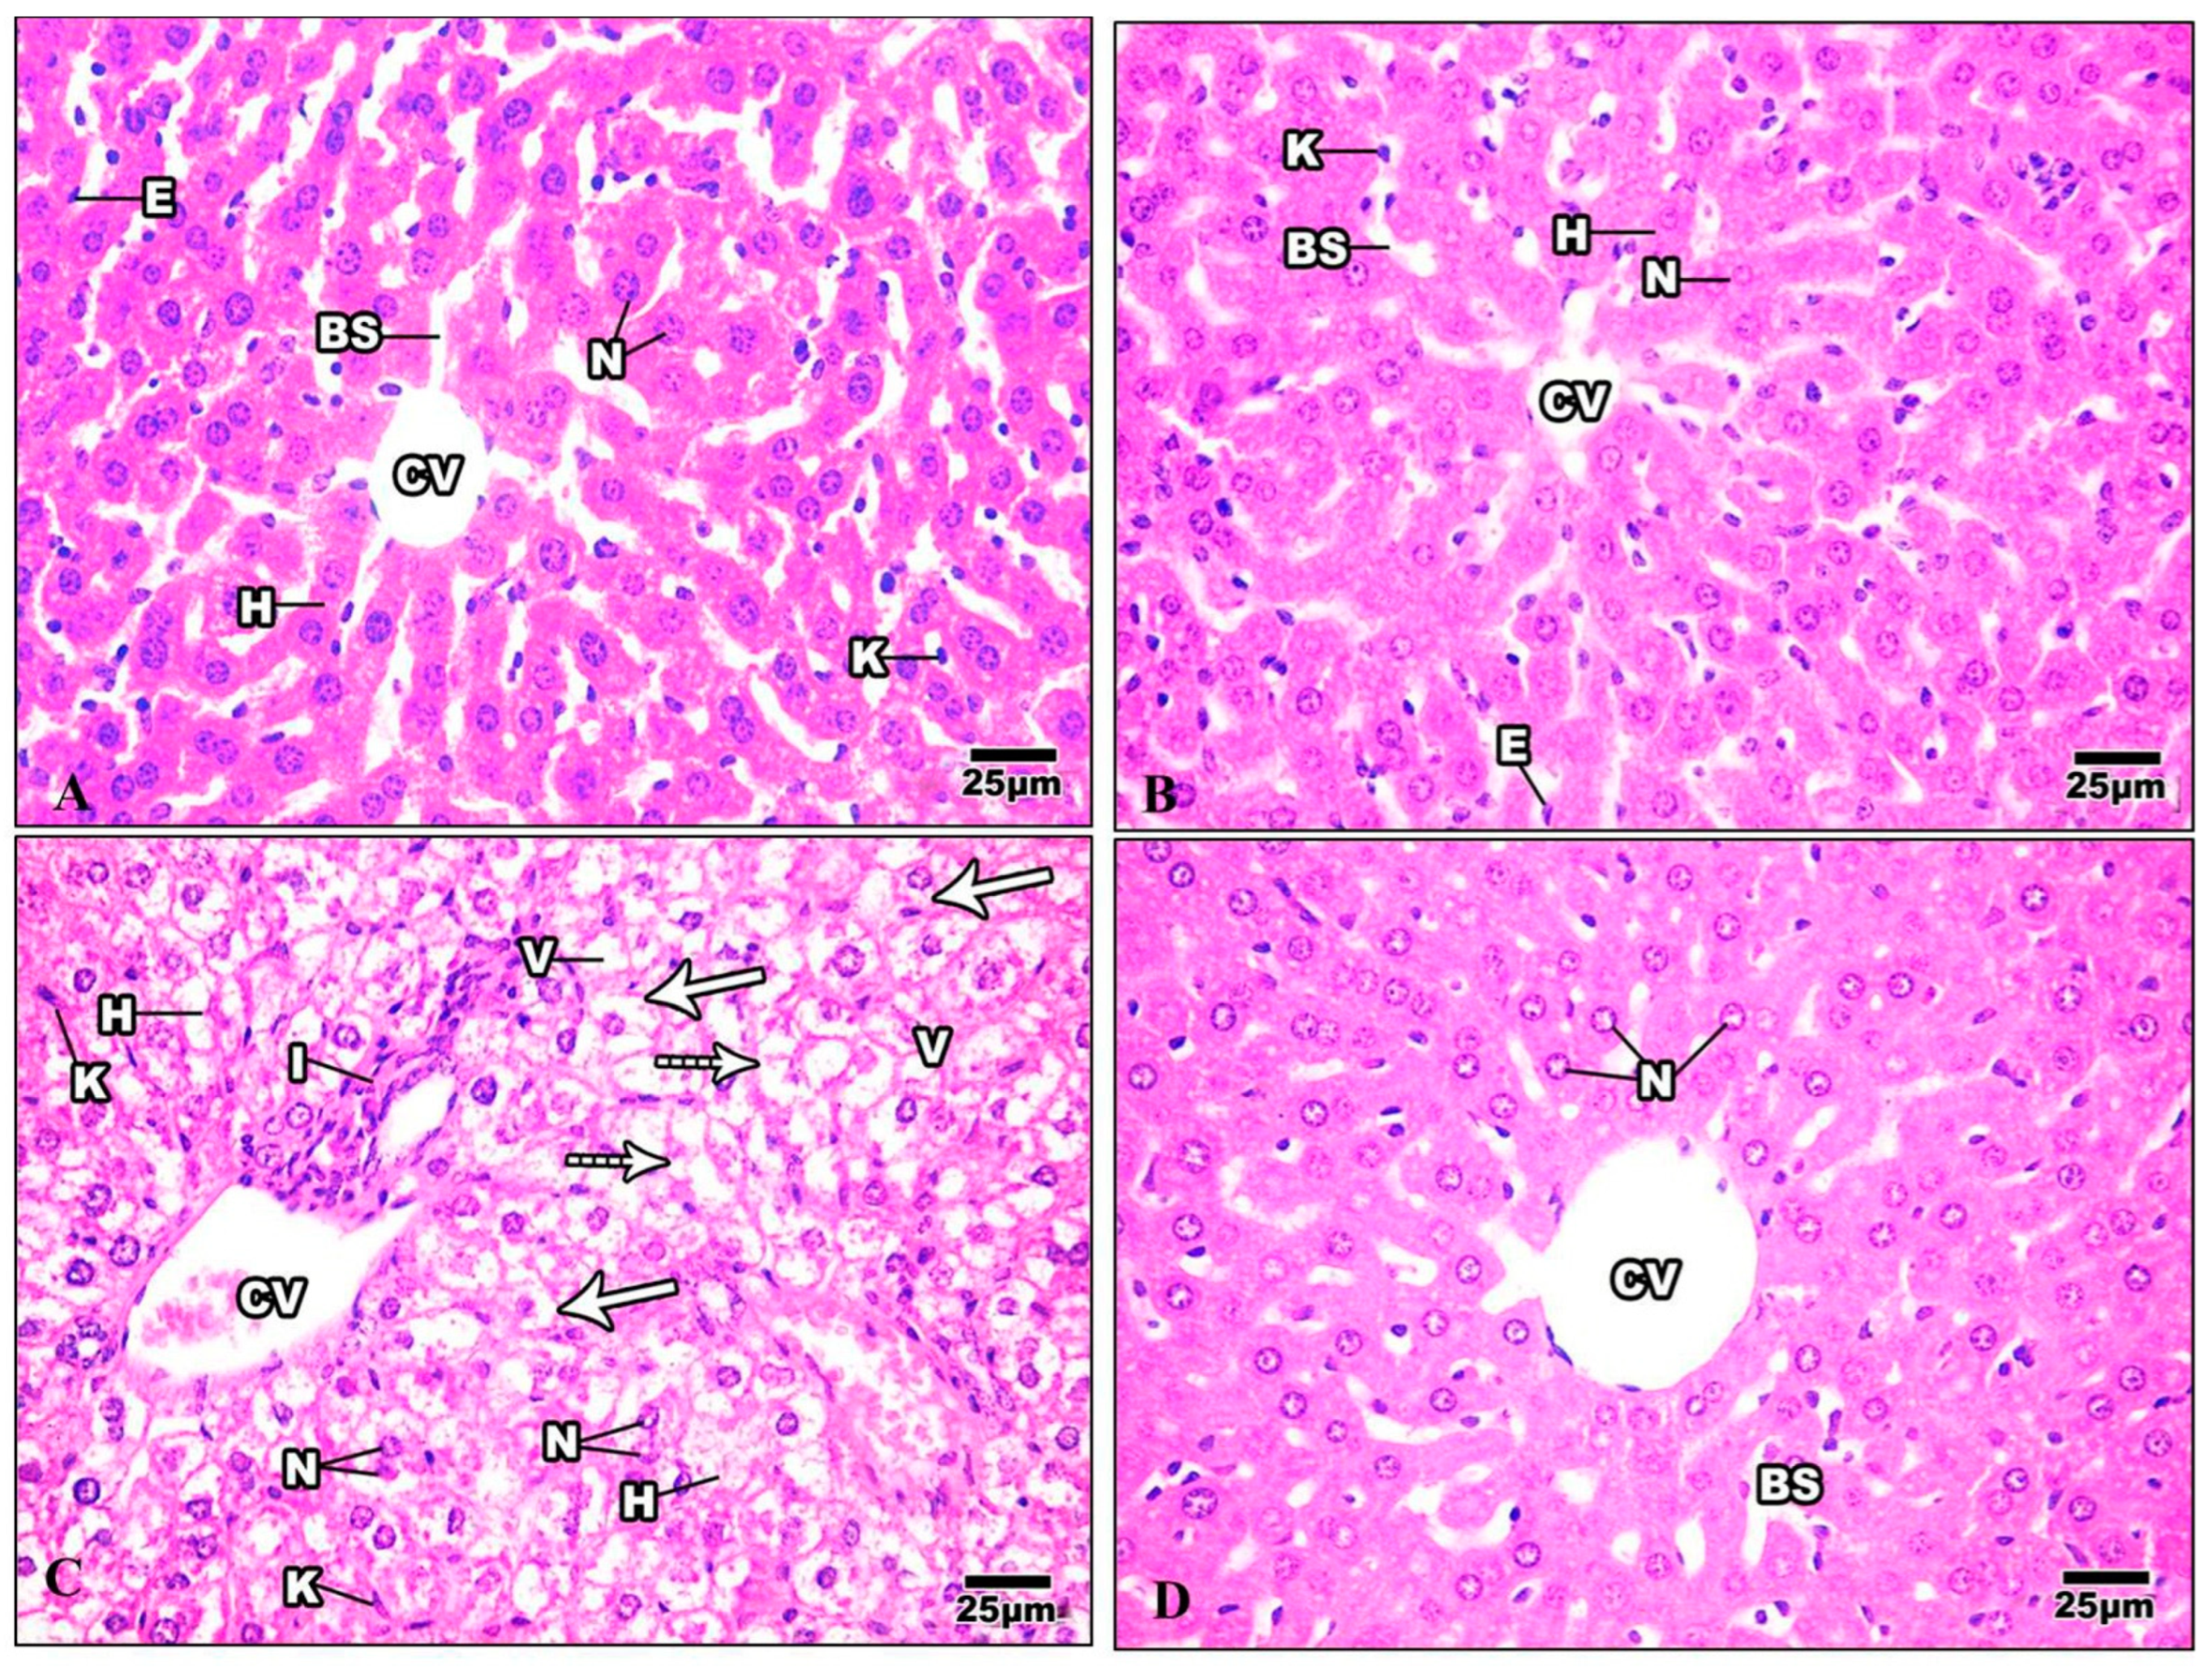

H&E-stained liver sections in the control group revealed a well-maintained hepatic lobular array with a well-preserved central vein architecture at the center, and radiating cords of hepatocytes were seen. The hepatocytes had a polyhedral shape and a granulated cytoplasm with tiny, homogeneous nuclei. Thin plates of these cells were spaced apart by large hepatic sinusoids, through which blood flows (Figure 9A). The hepatocytes of mice injected with Harmine appeared with spherical ovoid nuclei. Hepatic sinusoids filled the spaces between the plates and converged toward the central vein, lined by endothelial cells (Figure 9B). Liver sections of the HFD group showed variable histopathological changes, including distortion of the hepatic cellular architectures. Occurrences of cellular necrosis were observed in the liver of the HFD mice, as well as a big focal zone of injured hepatocytes, including numerous inflammatory cells. Unusually, large amounts of fat characterized widespread steatosis within the hepatocyte. They were greatly swollen and oval. It is possible to see a dilated, congested central vein exhibiting obvious endothelial lining degradation (Figure 9C). When compared to the HFD group, the liver’s histological structure in most diabetic mice treated with Harmine showed little degenerative changes. Hepatocyte strands partially reverted to their original structure, showing that the Harmine treatments enhanced recovery from HFD-induced liver injury. They showed good organization and a slight sinusoidal dilatation around the main vein (Figure 9D).

Figure 9.

Photomicrographs of liver sections of the control group and other treated groups. (A) photograph of the liver section of the control group showing hepatic lobular parenchyma of normal mice, which reveals polyhedral hepatocytes (H) with spherical or oval nuclei (N), blood sinusoids (BS) lined by endothelial cells (E), and Von Kupffer cells (K). (B) Liver section of Harmine group showing hepatic lobular parenchyma of a mouse. Polyhedral hepatocytes (H) were shown to have spherical or oval nuclei (N) and blood sinusoids (BS), which were lined by endothelial cells (E) and Von Kupffer cells (K). The central vein can be seen (CV). (C) The liver section of the HFD group shows foci containing inflammatory cells (I) surrounded by empty-looking areas devoid of hepatocytes. Also, the presence of karyolytic and irregularly shaped nuclei (N) can be observed, as well as the presence of damaged hepatocytes (H). Enlarged Von Kupffer cells (K), micro steatosis (arrows), and macro steatosis (dotted arrows) can be observed. V: cytoplasmic vacuolization; CV: central vein. (D) The liver section of the HFD mice was cured using Harmine, and hepatocytes with similar features to the control group can be seen, with mild blood sinusoidal dilatation (BS) around the central vein (CV). Some hepatocytes show the margination of the nuclear chromatin (N). (H & E; 400×).